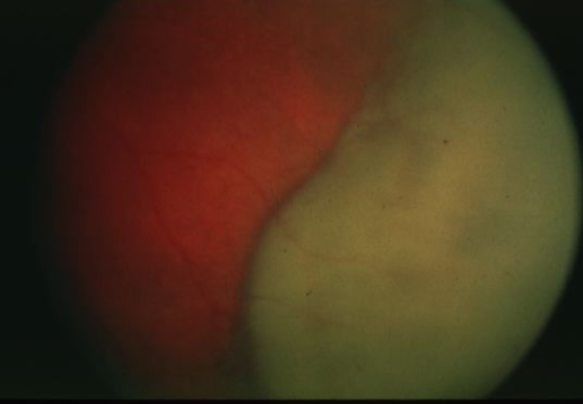

metastatic carcinoma

metastatic carcinoma

metastatic carcinoma

metastatic carcinoma

metastatic carcinoma

metastatic carcinoma

metastatic carcinoma

metastatic carcinoma

metastatic carcinoma